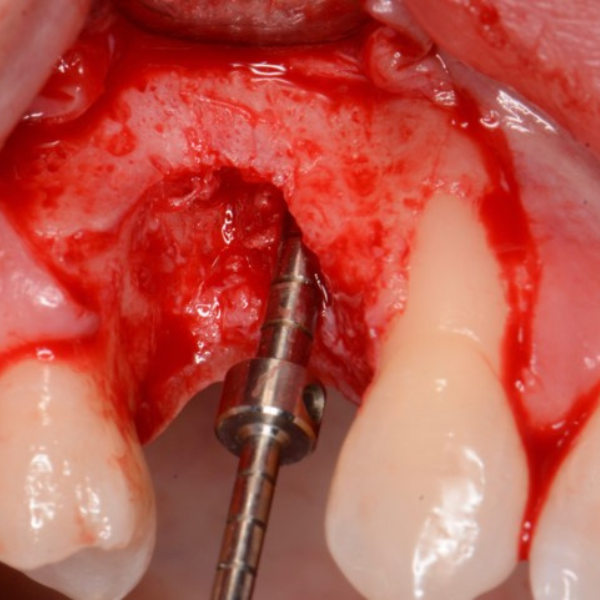

Anterior Implant Placement & Graft